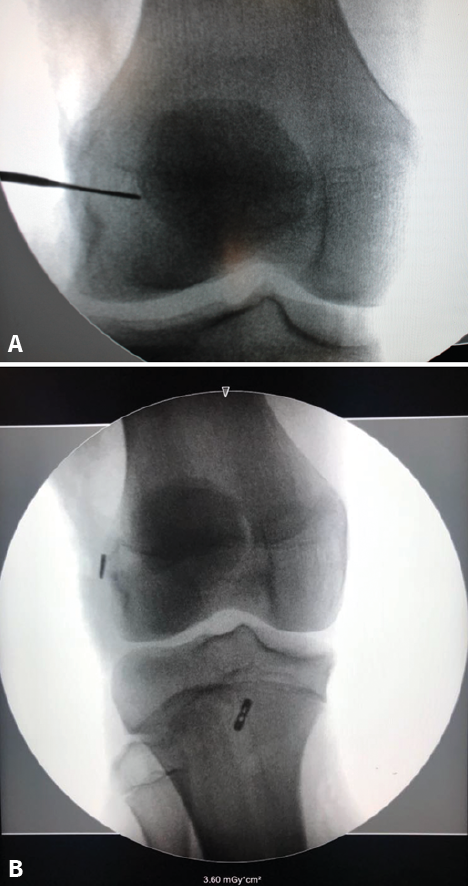

Although the findings are usually normal, plain radiographs can help discard other types of lesions. Tibial spine fracture (Figure 2) in children can occur with a clinical history and physical examination findings similar to those of ACL injuries(26). In addition, radiographs allow us to assess other lesions (epiphysiolysis, fracture-avulsion of the inferior pole of the patella or fractures of the tibial tuberosity) characteristic of pediatric patients(27). Therefore, anteroposterior under loading and lateral Rx views of both knees are needed in the case of suspected ACL injury.

Figure 2. Radiographs of the left knee in anteroposterior (A) and lateral (B) view in a 10-year-old boy, showing tearing of the displaced anterior tibial spine (arrow), corresponding to grade II of the classification of Meyers and McKeever.